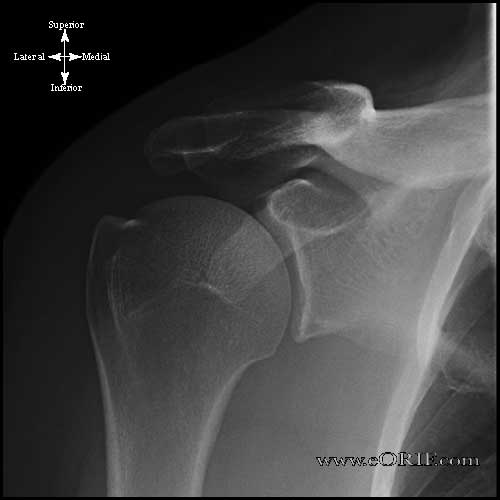

shoulder xray

Normal shoulder AP xray